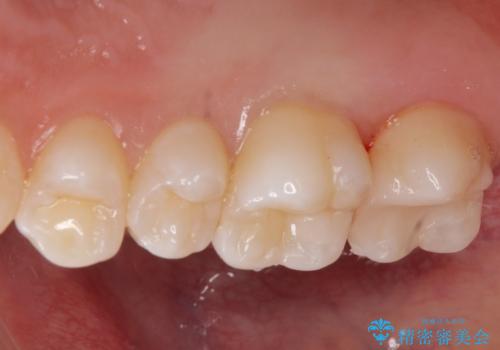

歯と歯の間の虫歯 e-maxインレーで修復

- 歯と歯の間に虫歯が見られたために、拡大鏡下でう蝕を取り除き、e-maxインレーで治療しました。

- e-maxインレー 7.7万円 費用は治療当時の料金となります

セラミックの素材は樹脂の素材に比べて虫歯の再発のリスクが低いです。